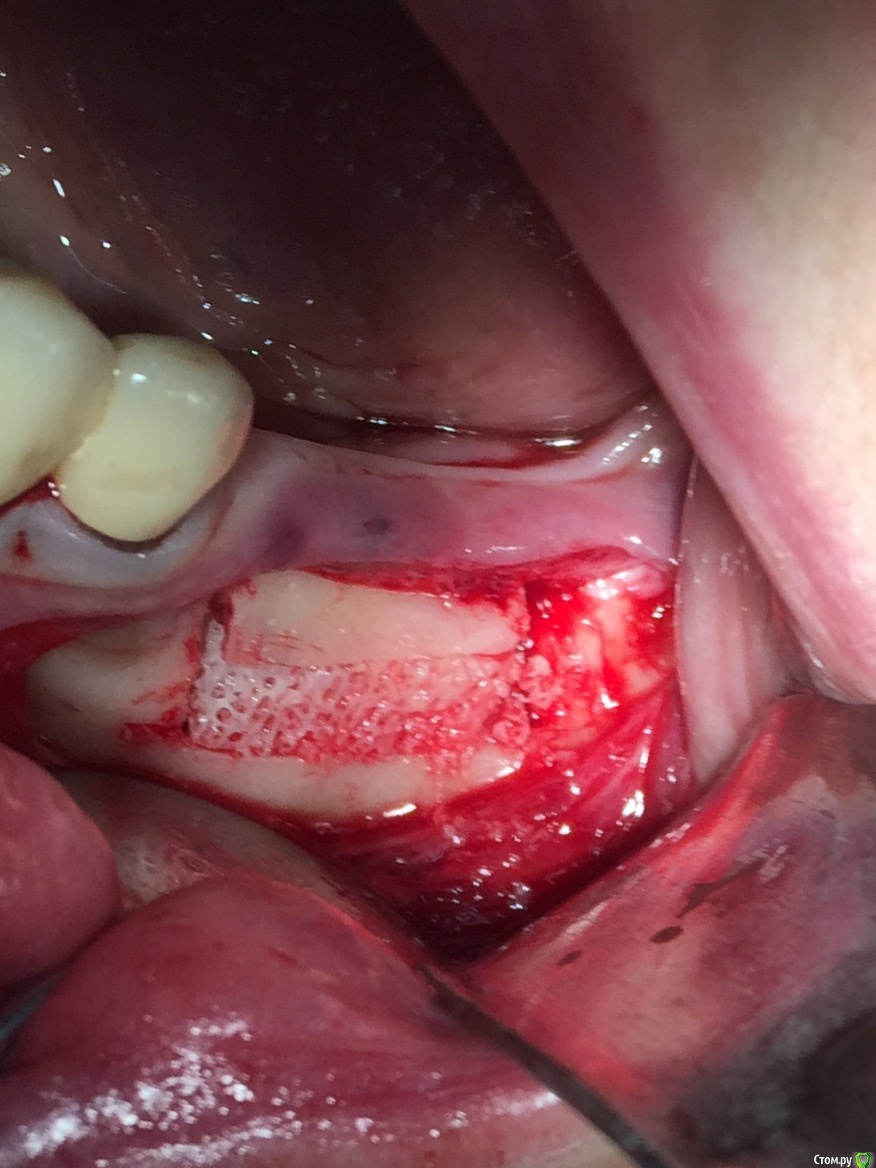

Andre_ Опубликовано 16 января, 2016 Поделиться Опубликовано 16 января, 2016 Скажите, пожалуйста, чем укрылись на 5-м фото Ссылка на комментарий

Глеб Митрофанов Опубликовано 16 января, 2016 Автор Поделиться Опубликовано 16 января, 2016 Скажите, пожалуйста, чем укрылись на 5-м фотоА-PRF Ссылка на комментарий